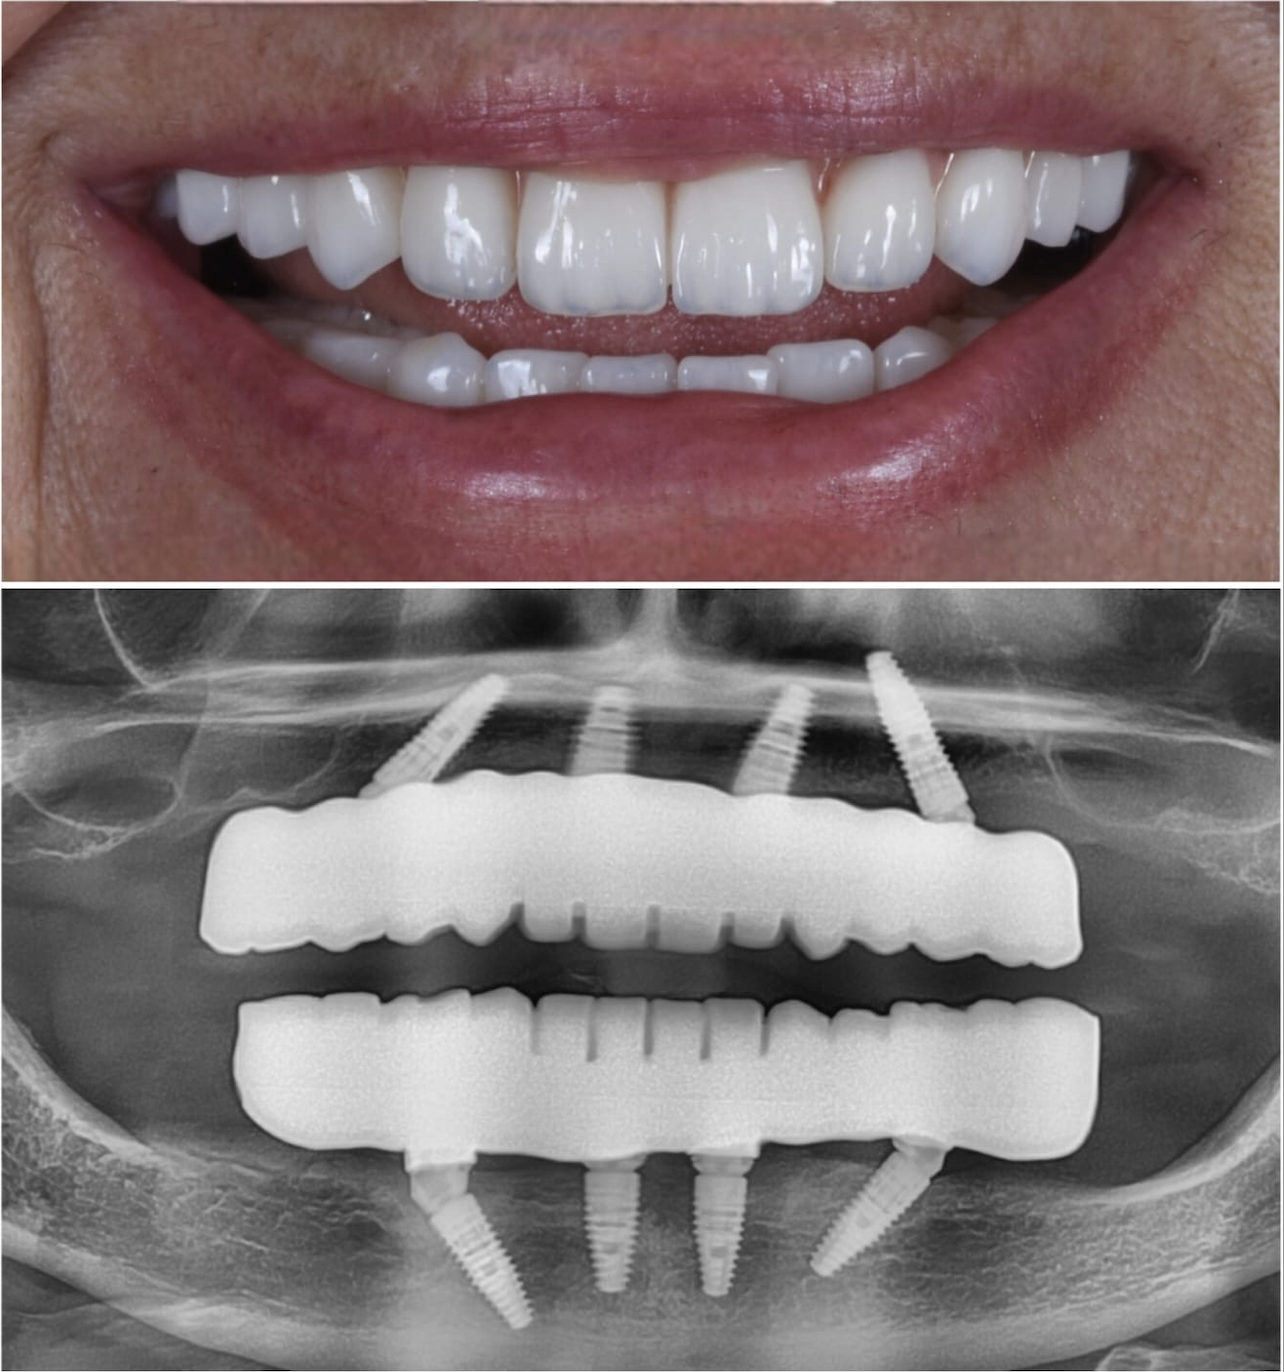

Patient Transformations

See the life-changing results of the ZAGA Philosophy.

Immediate Loading Success

Before

Before treatment

After

After treatment